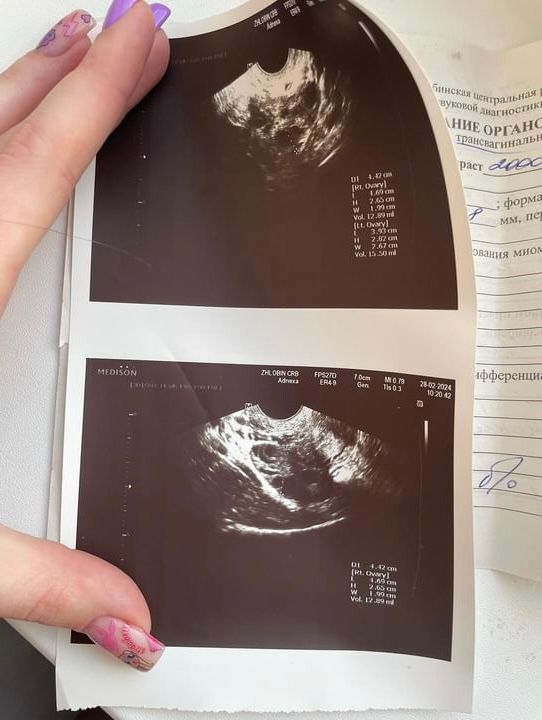

Исходя из результатов узи, можно сделать вывод, что яичники увеличены в размерах и каждый имеет более 9 фолликулов. Я предположила, что это МФЯ и посоветовала обратиться к гинекологу-эндокринологу. (Я конечно могу ошибаться)